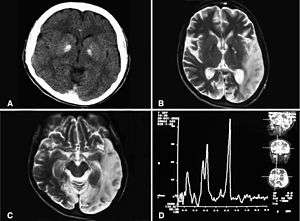

| Basal ganglia calcification, cerebellar atrophy, increased lactate; a CT image of a person diagnosed with MELAS | |